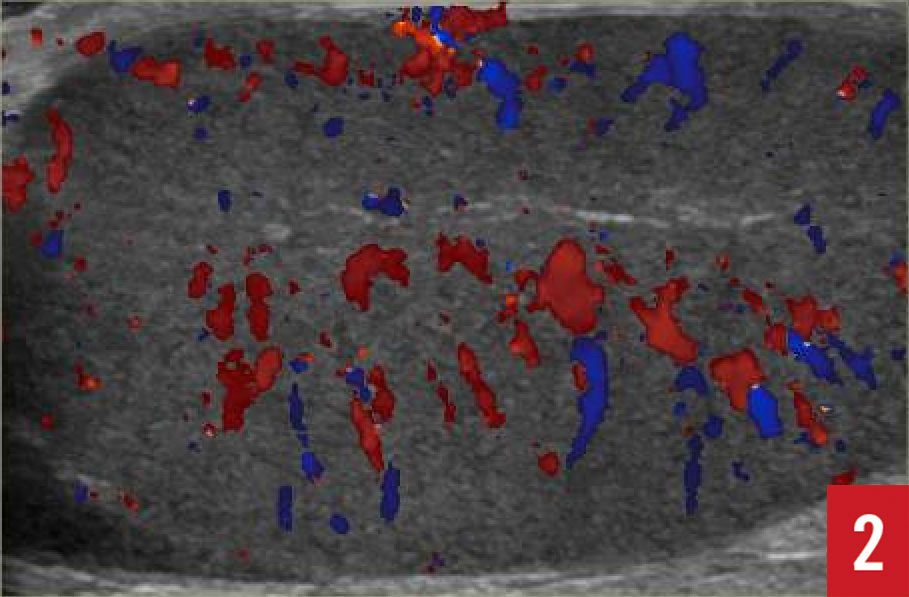

At 4 hours after the onset of pain, testicular ultrasonography was performed in view of the persistent mild left testicular tenderness noted during the initial examination. The results revealed left testicular torsion with an absence of blood flow to the left testis (Figures 1-5). The scrotal skin was of normal thickness with no hyperemia. The testis demonstrated normal size and echogenicity, but the epididymal head was enlarged and ill-defined, with prominent cystic features indicative of infarction. A small hydrocele was also present. The spermatic cord was normal, with no signs of torsion in the inguinal canal.

Figure 2: The right testicle had normal flow